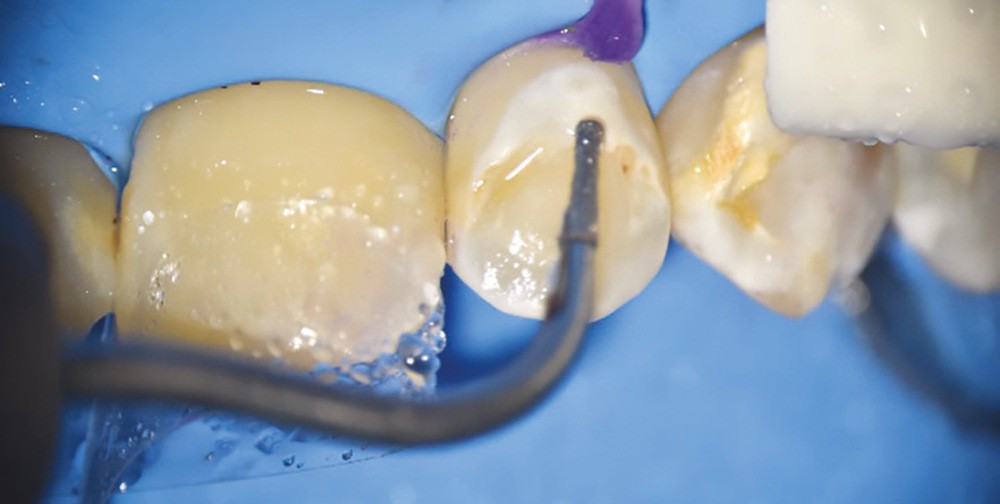

• Traitement invasif a minima : il concerne les lésions carieuses cavitaires ou non avec atteinte dentinaire (à partir du 1/3 moyen dentinaire), soit ICDAS 3 à 6. Dans ce cas, la priorité est de préserver la dent d’une effraction pulpaire éventuelle (recommandations de l’ESE) [4]. C’est pourquoi, lors du traitement de lésions carieuses profondes (ICDAS 4 à 6), il faut dans tous les cas réaliser une éviction sélective, réaliser une préparation a minima (favoriser les préparations de type fente (« slot ») ou tunnel lorsque l’indication se pose) et utiliser un matériau de restauration de choix, soit composite, soit un ciment verre ionomère (CVI), soit des matériaux à base de silicate de calcium ou encore les nouveaux composites enrichis en minéraux (fig. 7 à 9). Ces préparations a minima peuvent être réalisées avec des fraises de petits diamètres (fig. 10 et 11).